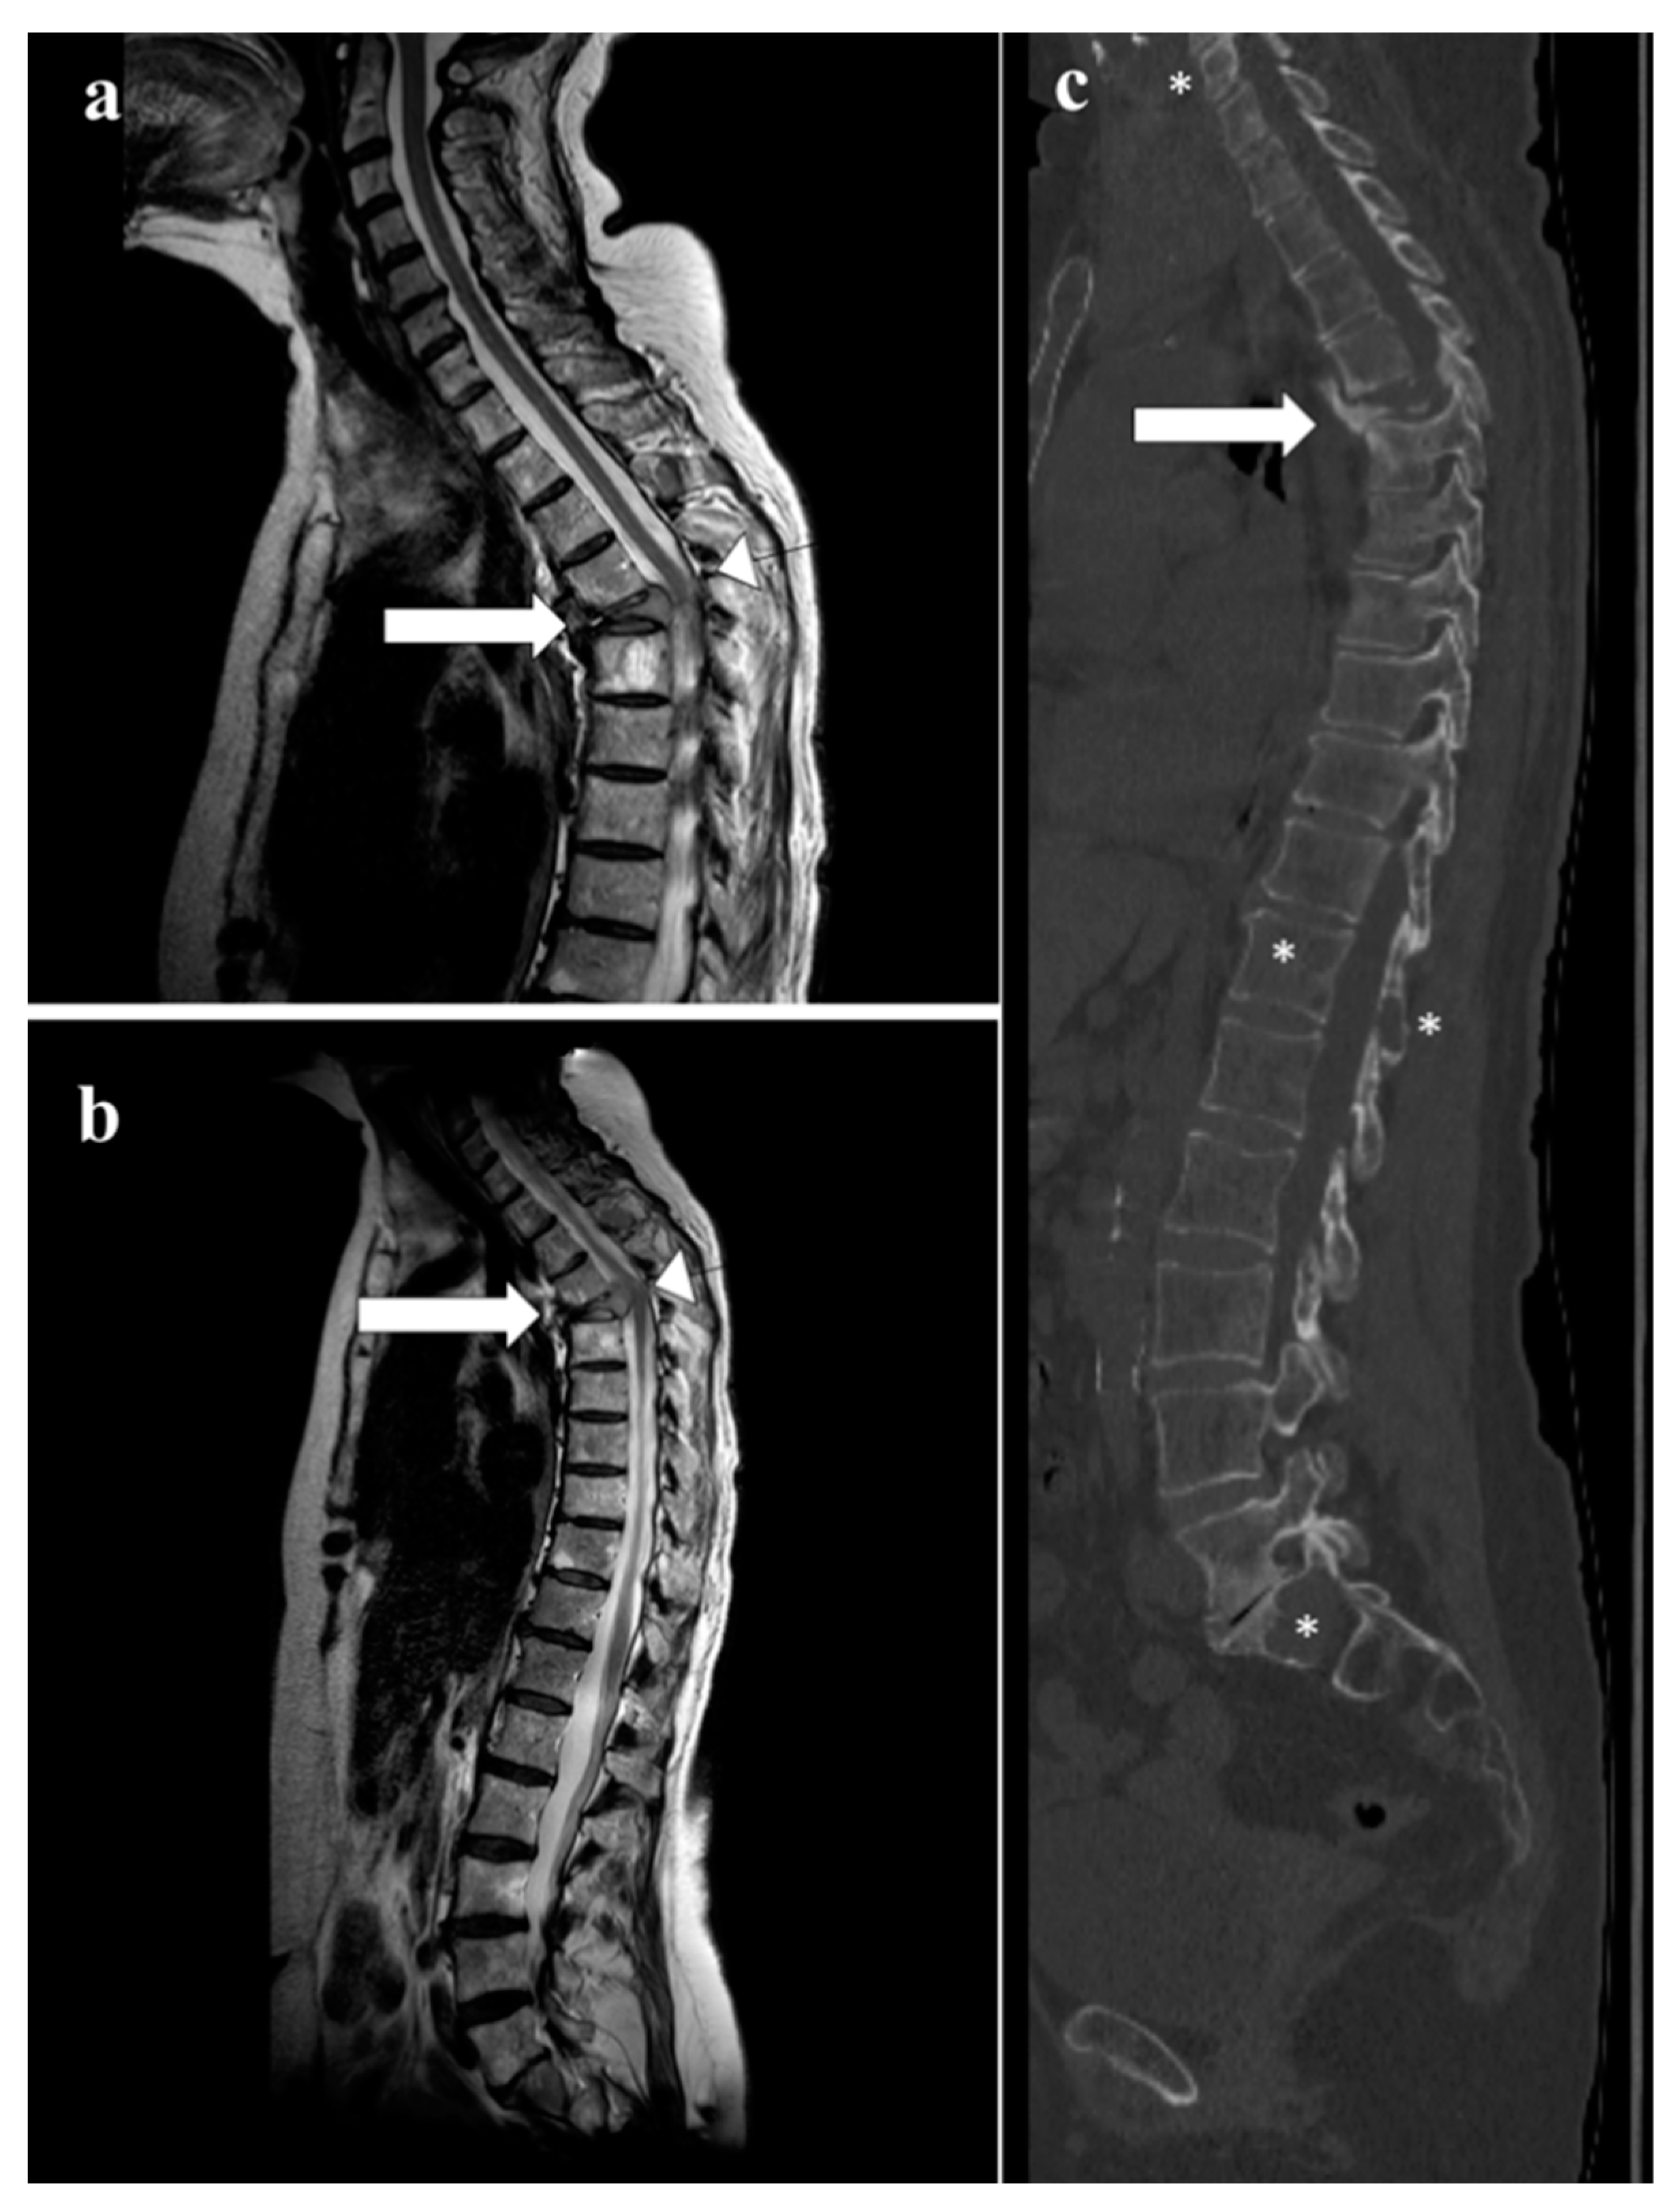

- Sureka, J.; Samuel, S.; Keshava, S.; Venkatesh, K.; Sundararaj, G. MRI in patients with tuberculous spondylitis presenting as vertebra plana: A retrospective analysis and review of literature. Clin. Radiol. 2013, 68, e36–e42. [Google Scholar] [CrossRef]

- Kaila, R.; Malhi, A.M.; Mahmood, B.; Saifuddin, A. The Incidence of Multiple Level Noncontiguous Vertebral Tuberculosis Detected Using Whole Spine MRI. J. Spinal Disord. Tech. 2007, 20, 78–81. [Google Scholar] [CrossRef]

- Haghighatkhah, H.; Jafroodi, Y.; Taheri, M.S.; Pourghorban, R.; Dehkordy, A.S. Multifocal Skeletal Tuberculosis Mimicking Langerhans Cell Histiocytosis in a Child: A Case Report with a Long-Term Follow-Up. Iran. Red. Crescent. Med. J. 2015, 17, e19942. [Google Scholar] [CrossRef] [PubMed]